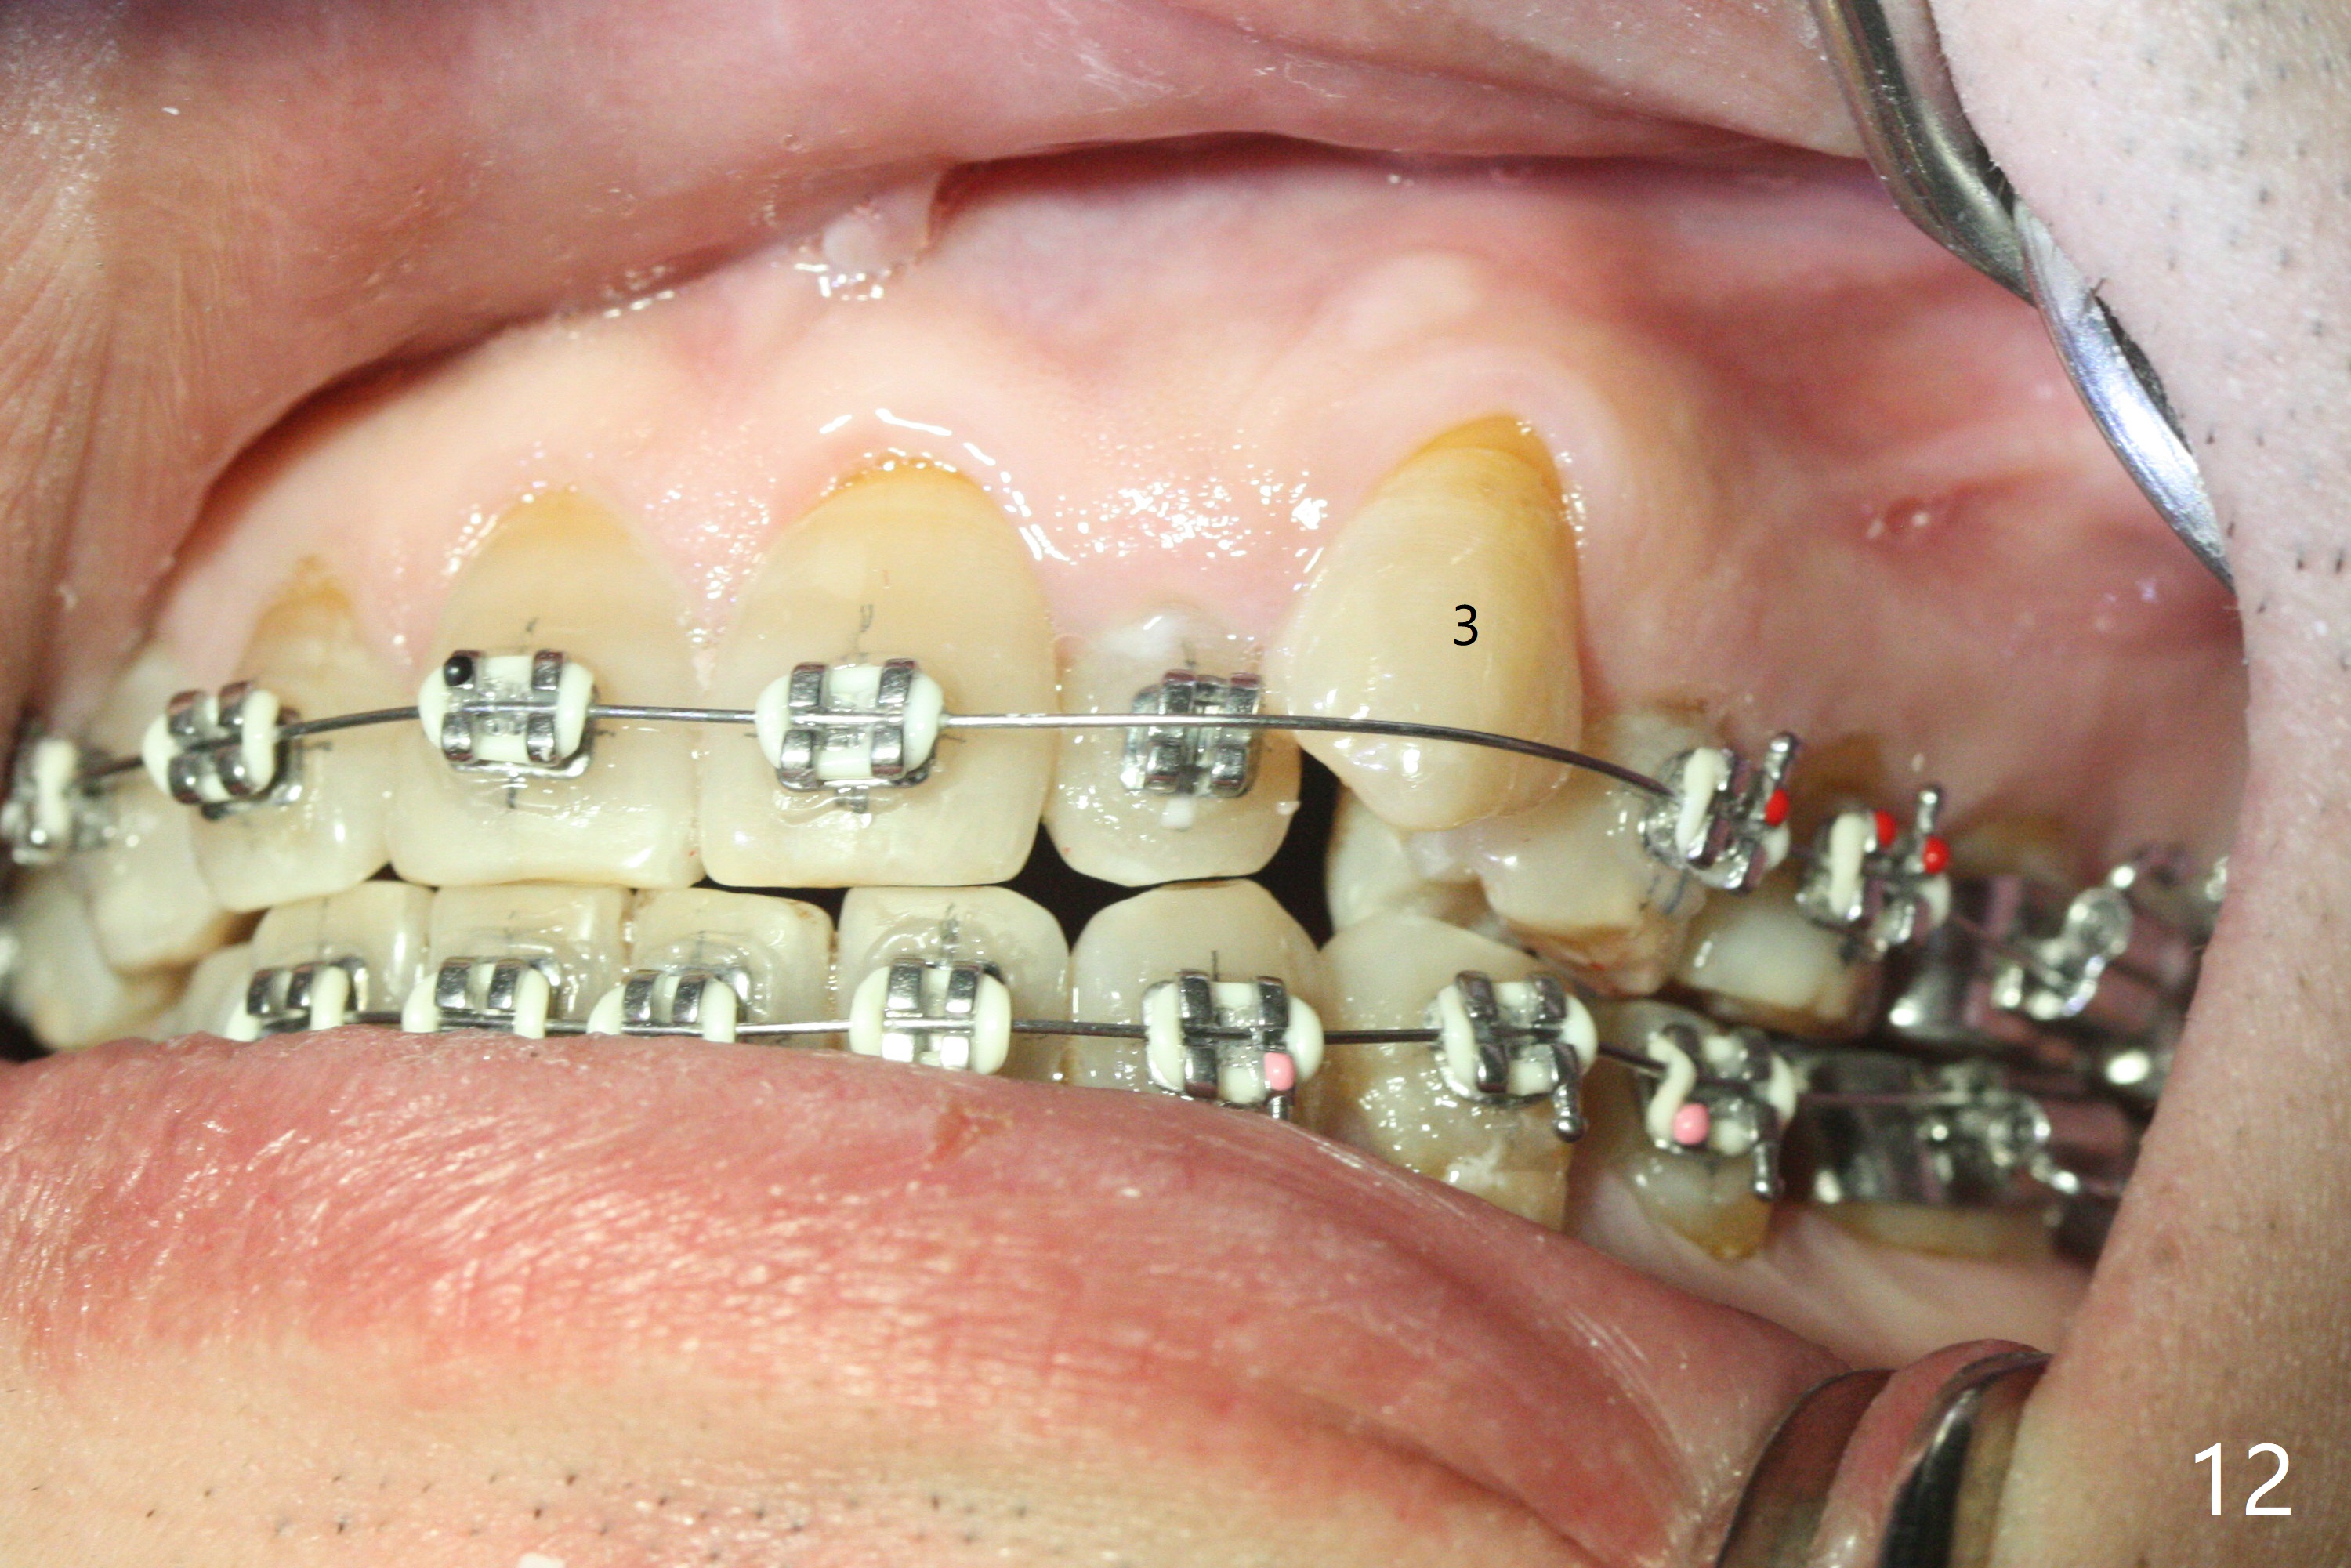

A 40-year-old man requests orthodontics after #17 and 32 extraction. UL5 is missing (Fig.1), while the upper midline deviates to the left (Fig.2 arrow) with crowding between UL2 and 3 (Fig.3). The main goal is to retract UL5 distal and move the upper midline to the right to alleviate UL anterior crowding. Implant will be not needed. To monitor potential root resorption associated with tooth movement, preop PAs are taken (Fig.4-7). The space for an implant at UR5 is narrow. UR4 needs to be distalized using UR7 or a miniimplant distal to UR7 as an anchor (Fig.8). UR4 and 3 will be repositioned to establish Class I occlusion (Fig.9). The space gained by UR4 distalization may be enough to correct the upper midline deviation and UL3 malposition (Fig.10). Brackets will be placed in the lower arch in spite of the normal alignment (Fig.11). UL2 and 3 brackets are unable to be engaged to 14 niti wire (Fig.12). Next visit try to engage UL2 bracket. If not, save the old wire for possible future reuse. Closed spring is placed with 18 ss wire <3 months post banding (coronavirus). Three weeks post closed spring between UR4-7, UR3,4 are being distalized (Fig.13). Distalization of UR4 is not much in 5.5 months (Fig.14,15). It seems necessary to use a miniimplant distal to UR7 as an anchor (Fig.16 white circle), place a long hook mesial to UL4 (more or less root movement instead of tilt) and place the same closed spring between the anchor and hook. In spite of the fact that UR4 seems to have been completely distalized and that UR2 is being distalized 8 months post banding (Fig.18), a 8 mm long mini-implant is placed in the maxillary tuberosity with minimal local anesthetic (Fig.17,19). A longer closed spring (18 mm) is placed between the implant and UR3 hook (Fig.20). Next appointment a lingual button will be placed at UR4 for rotation, while a post hook mesial to UR3 for torque. UR3 distalizes with the help of UR mini-implant, which is unfortunately loose. Next visit place lingual button at UR4 (Fig.21 arrow) to distalize the lingual cusp. Crimpable power hook is placed mesial to UR2 for distalization (for root torque, Fig.22). If it works, remove the wire and reposition the hook for UR1 next visit. UR2 is distalized in one appointment (~ 1 month, Fig.23, as compared to Fig.22). With lingual button at UR4, rotation seems to have been corrected shortly (Fig.24 arrow).